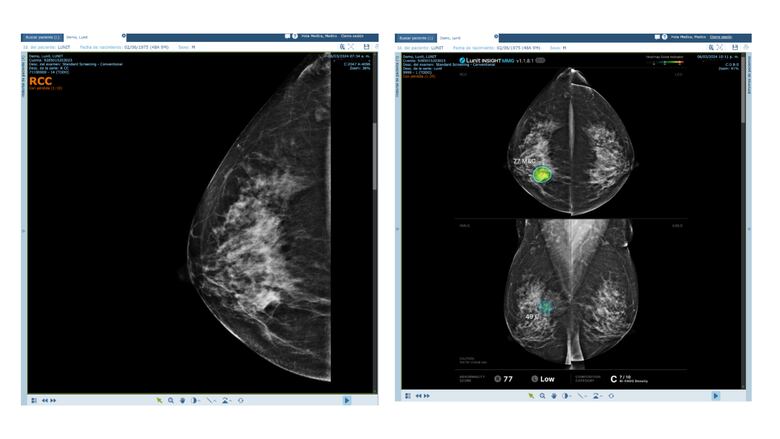

La apuesta se fortalece con una alianza estratégica con Lunit, líder mundial en IA aplicada a la radiología. A través de algoritmos avanzados, hoy es posible detectar de manera temprana cáncer de mama y hasta 11 patologías pulmonares, con un nivel de precisión que mejora las oportunidades de tratamiento y supervivencia. La innovación no solo beneficia a los pacientes: también optimiza recursos hospitalarios, apoya a los médicos en diagnósticos más rápidos y ayuda a priorizar casos de alto riesgo.